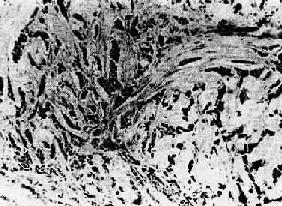

1.鳞状细胞(squamous cell carcinoma)简称鳞,常发生在身体原有鳞状上皮覆盖的部位,如皮肤、口腔、唇、子宫颈、阴道、食管、喉、阻茎等处。有些部位如支气管、胆囊、肾盂等处,正常时虽不由鳞状上皮覆盖,但可通过鳞状上皮化生而发生鳞状细胞。此肉眼上常呈菜花状,也可因组织坏死脱落而形成溃疡。组织也同时向深层作浸润性生长。镜下,在分化好的鳞状细胞的巢中,细胞间还可见到细胞间桥,在巢的中央可出现层状的角化物,称为角化珠(keratin pearl)或珠(图7-12)。分化较差的鳞状细胞无角化珠形成,甚至也无细胞间桥,细胞呈明显的异型性并见较多的核分裂像。

鳞状细胞<a href=癌"/>

图7-12 鳞状细胞

图示典型的细胞巢,其中两个巢中央形成同心圆状的角化珠